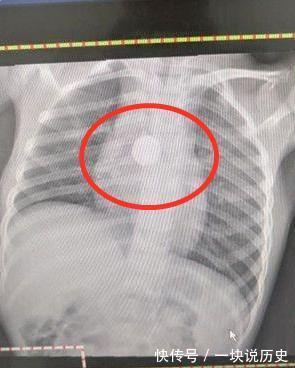

位于澳洲墨尔本的琪拉女士万万没有想到自己5岁的女儿这段时间竟然开始暴瘦了,以往孩子从来都没有出现过这样的情况,毕竟孩子一直都很健康,这到底是怎么回事呢?为了查证原因,李女士带着女儿去医院做了一个检查。不过就在做x光的时候,医生有点懵了。孩子的胸前有一个非常明显的圆形的"项链",可是就在下一刻李女士说出来的话,让医生察觉到了问题所在。

琪拉女士说道"我家孩子没带项链啊。"听到这句话后,医生又看了看小女孩的脖子处,顿时恍然大悟。只见小女孩根本没有戴项链,因此小女孩肯定是因为不小心吞食了什么异物,才会在拍X光的时候拍出个"项链"。

所幸及时发现了问题所在,仔细检查后,医生发现在小女孩的喉咙处卡了一颗纽扣电池。经过手术后,电池也顺利地取了出来,虽然小女孩的喉咙有一些受损,之后几天可能会影响到进食,但所幸没有耽误太久,这颗纽扣电池没有对孩子造成更严重的伤害。